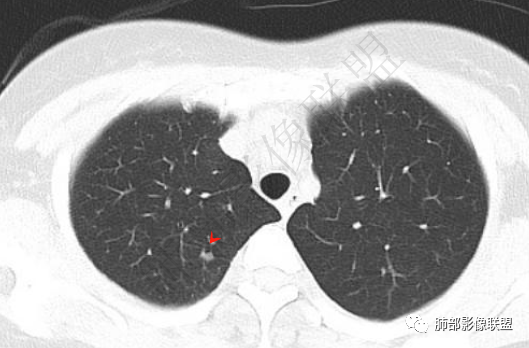

肺内多发小斑片状高密度影,密度不均匀,边缘稍平直

胸膜多个结节,附近胸壁脂肪间隙密度增高,提示有胸壁蔓延或侵犯。

胸膜区病灶周围肺内有小斑片状影,内有条索影,而非放射状,提示提示病灶累及肺内。周围渗出明显——良性肿瘤排除